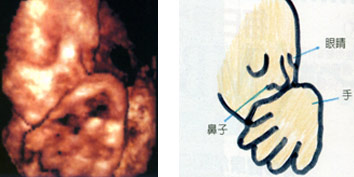

怀孕34周

怀孕34周

这张是3D超音波照,虽然有些模糊,但还是可以看到宝宝的五官,待宝宝出生后,就可以比对一下像不像啰?

怀孕35周

怀孕35周

可爱的胎儿,就像只小猫一般,卷曲着手在脸部前面,睡得香甜。

怀孕36周

怀孕36周

因为角度的关系,让胎儿脸部前方的手,看起来似乎比脸还大呢!